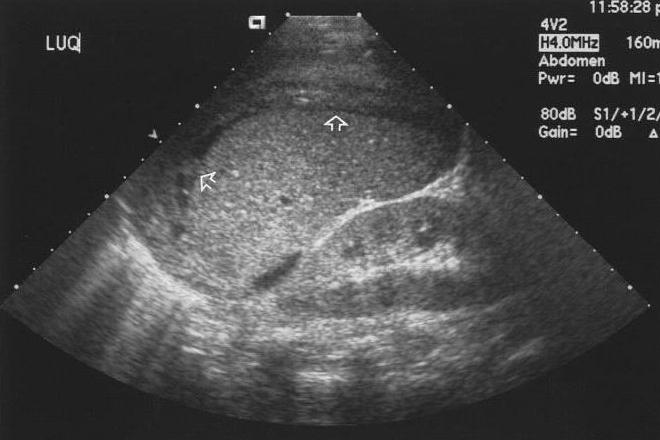

Ultrasonido en el primer trimestre de embarazo

Es importante que el médico de primer contacto aprenda a utilizar e interpretar ultrasonido, ya que proporciona la confirmación de un diagnóstico, pronostica como será el proceso y la culminación de un embarazo. El Artículo proporciona 10 recomendaciones para la evaluación ultrasonográfica del primer trimestre de embarazo en el primer